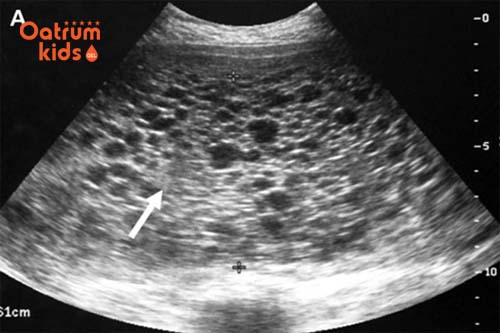

Siêu âm được xem là phương pháp chính xác nhất giúp các mẹ chẩn đoán xem mình đã mang thai hay chưa. Tuy nhiên siêu âm chỉ có kết quả chính xác khi thai đã được tầm 5 đến 7 tuần. Còn nếu thai mới được 2 tuần thì việc siêu âm sẽ chưa có kết quả.

Các chuyên gia y tế cho rằng một chu kỳ mang thai của mẹ bầu sẽ kéo dài 40 tuần được tính từ ngày xuất hiện kinh nguyệt cuối cùng. Do đó, ở tuần thứ 2 của thai kỳ chỉ là giai đoạn trứng rụng nên chưa có gì có thể đảm bảo bạn đã thụ thai. Chính vì vậy nếu siêu âm ở thời điểm này được coi là hơi sớm nên sẽ không có kết quả.

Siêu âm thai 2 tuần tuổi chưa thế biết chính xác được hình ảnh thai nhi.

Ngay cả khi bạn siêu âm đầu dò cũng không thể phát hiện được ra việc mình có thai hay không. Tốt nhất nếu muốn biết chính xác thì bạn cần đợi tầm 6 tuần trở lên, đây là thời điểm lý tưởng nhất cho lần siêu âm đầu tiên mà các mẹ nên biết. Do đó dù có đi siêu âm lúc này thì các bác sỹ cũng sẽ hẹn mẹ vào các đợt tiếp để siêu âm.